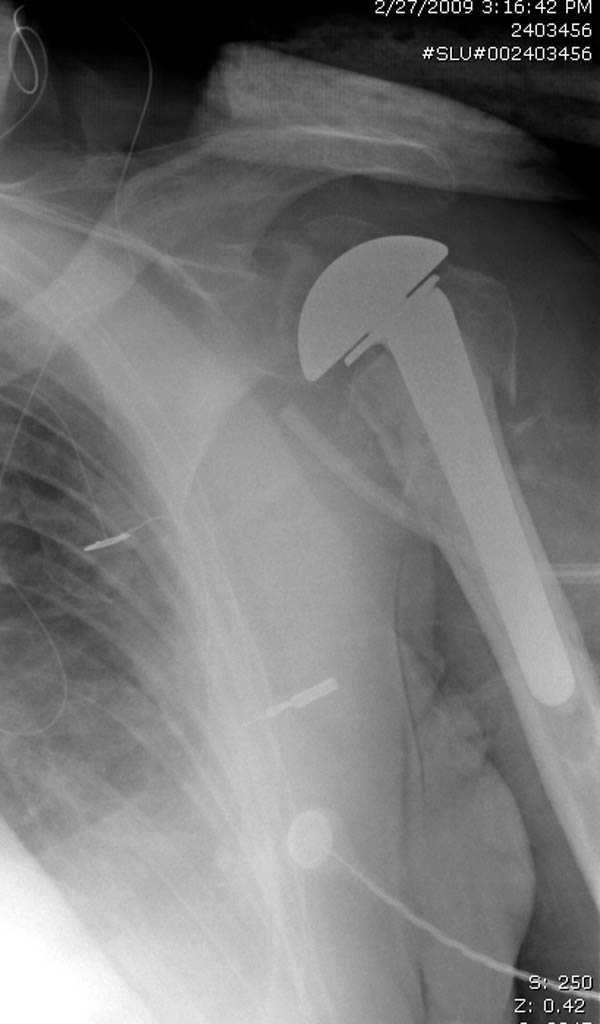

дополнительные снимки по протезированию